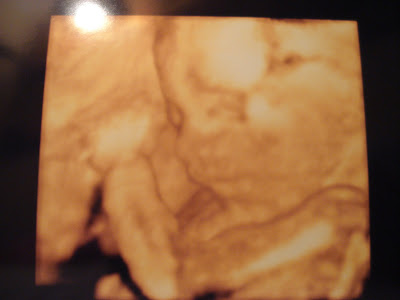

Já vai tanto tempo desde que aqui escrevi, e tanta coisa se passou! Passado dia 12 foi a ecografia morfológica das 20 semanas. Fizemos a ecografia 4D e fomos apresentadas à nossa filhota, live from inside Lu. A pimpolha estava pendurada de cabeça para baixo, bem aninhada de ladecos de encontro à mãe. Portanto, de costas para o mundo. Foi difícil de convencer a mostrar a cara, pois tinha sempre a mão esquerda fechada de encontro à cara. Continuo a pensar que temos uma chuchadora. Lá conseguimos ver-lhe a carinha. Laroca por sinal, mas eu sou parcial. Ainda é magrinha. É caso para dizer que é pele e osso, mas já se vê tudo, nariz, olhos, orelha, maças do rosto, lábios. Do que vejo fico feliz, sai à mãe! Os lábios grossos, nota-se, como que a dizer marca registada ®. As maças do rosto também são como as da Lu. Num momento, faz nitidamente uma birra: esfrega a cara, nariz como se tivesse impertinente para dormir, vira a cara e tapa a cabeça com o braço como que a dizer: deixem-me da mão, quero estar sossegada!

A nossa filhota é linda, e encontro-me definitivamente apaixonada por ela. À noite, antes de dormirmos, a mamã Lu deixa-nos brincar um bocadinho. Fico ali a falar com ela, a dar-lhe beijinhos, e a sentir os pontapés que já se fazem sentir. Está quase sempre do mesmo lado: do lado esquerdo. Às vezes encosto o ouvido à barriga e fico a tentar ouvir. Tento distinguir os sons da mamã, dos que faz a filhota nas suas cambalhotas.